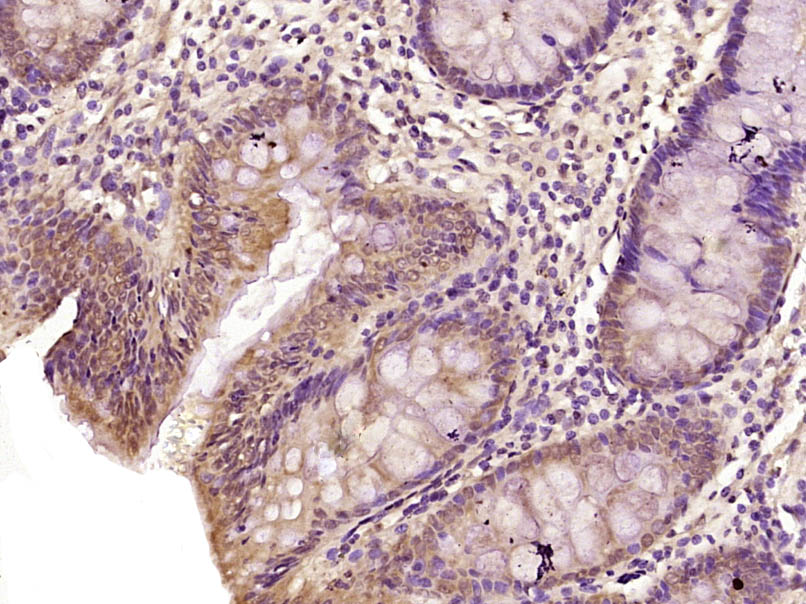

Paraformaldehyde-fixed, paraffin embedded (Human colon); Antigen retrieval by boiling in sodium citrate buffer (pH6.0) for 15min; Block endogenous peroxidase by 3% hydrogen peroxide for 20 minutes; Blocking buffer (normal goat serum) at 37°C for 30min; A